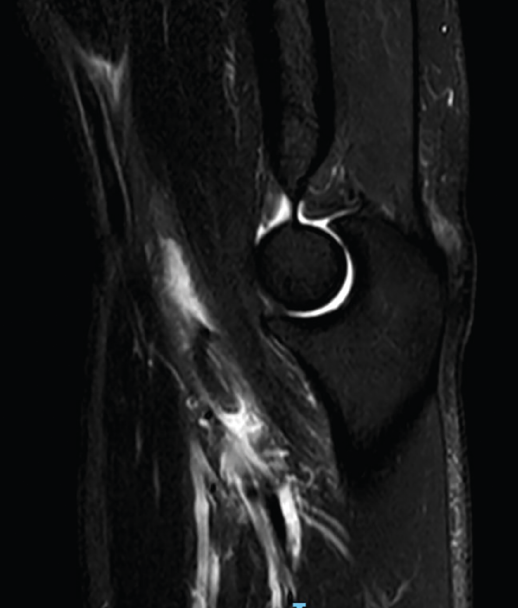

Figura 4. Corte sagital de resonancia nuclear magnética en el que se identifica una rotura completa del tendón del bíceps distal con 2 cm de retracción.

La bursitis es típicamente hipointensa en T1 con realce tras la administración de gadolinio y presenta halo periférico en T2. La RNM es especialmente útil en el diagnóstico diferencial de la bursitis con otras entidades que generan efecto masa en la fosa antecubital(26). Aunque las secuencias y posiciones típicas de la RNM suelen ser suficientes para realizar una valoración correcta del bíceps distal (Figura 4), existe la posición llamada de FABS (flexed, abducted, supinated) que proporciona una imagen longitudinal del tendón desde la unión miotendinosa hasta su inserción en la tuberosidad radial en un solo corte(27). El paciente se coloca en decúbito prono, con el codo en flexión de 90°, el hombro en abducción máxima y el antebrazo en supinación máxima, permitiendo identificar y cuantificar lesiones parciales, roturas completas y tendinosis, y siendo de gran utilidad en aquellos pacientes con una constitución física que dificulte la correcta exploración física.